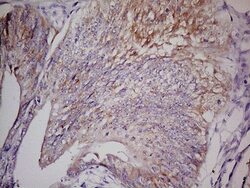

- Immunohistochemical staining of paraffin-embedded human gastric cancer using mouse anti-LGR5 clone UMAB212 (UM800104) at 1:400 with GBI Polink2 Broad HRP DAB detection kit (D22-110); pretreatment of tissue prior to stain with heat-induced epitope retrieval buffer from GBI Labs TEE pH 9.0 (B21-100) using pressure chamber for 3 minutes at 110°C is required for optimal staining. Shown here strong cytoplamic tumor cells.